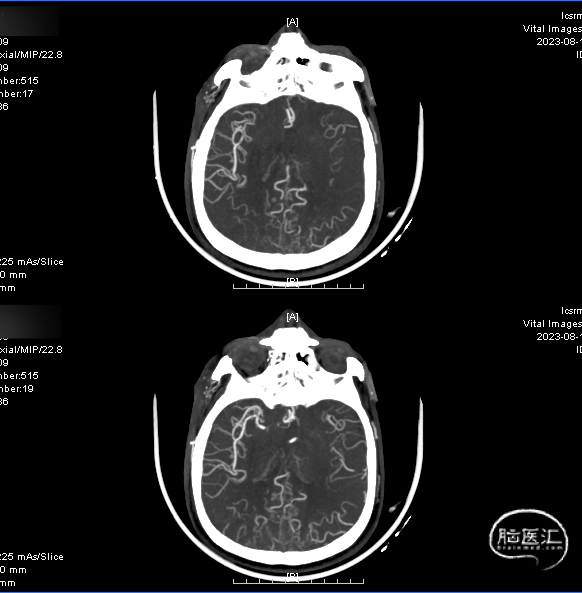

术前CTA:双侧颈内动脉闭塞,代偿可。

术前CTA:颅内代偿可。

右侧颈总正侧位:见右侧颈内动脉闭塞,颅外血管代偿良好。

左椎正侧位:椎基底动脉未见异常,可见部分代偿。

左颈总正侧位:左侧颈内动脉闭塞,可见血管残端。